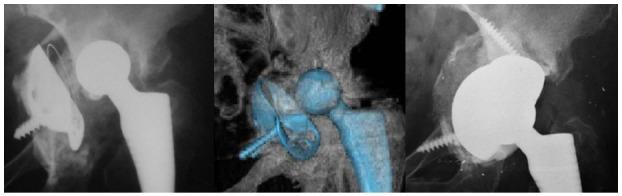

使用多孔钽组件的髋臼翻修术:一项随访5至10年的回顾性研究。

Acetabular revisions using porous tantalum components: A retrospective study with 5-10 years follow-up.

To evaluate the clinical and X-ray results of acetabular components and tantalum augments in prosthetic hip revisions.

Fifty-eight hip prostheses with primary failure of the acetabular component were reviewed with tantalum implants. The clinical records and X-rays of these cases were retrospectively reviewed. Bone defect evaluations were based on preoperative CT scans and classified according to Paprosky criteria of Radiolucent lines and periprosthetic gaps; implant mobilization and osteolysis were evaluated by X-ray. An database was created and statistical analyses were performed with SPSS software (IBM SPSS Statistics for Windows, version 23.0). Statistical analyses were carried out using the Student's test for independent and paired samples. A value of < 0.05 was considered statistically significant and cumulative survival was calculated by the Kaplan-Meier method.

RESULTS

The mean follow-up was 87.6 ± 25.6 mo (range 3-120 mo). 25 cases (43.1%) were classified as minor defects, and 33 cases (56.9%) as major defects. The preoperative HHS rating improved significantly from a mean of 40.7 ± 6.1 (range: 29-53) before revision, to a mean of 85.8 ± 6.1 (range: 70-94) at the end of the follow-up (Student's test for paired samples: < 0.001). Considering HHS only at the end of follow-up, no statistically significant difference was observed between patients with a major or minor defect (Student's test for independent samples: > 0.05). Radiolucent lines were found in 4 implants (6.9%). Postoperative acetabular gaps were observed in 5 hips (8.6%). No signs of implant mobilization or areas of periprosthetic osteolysis were found in the x-rays at the final follow-up. Only 3 implants failed: 1 case of infection and 2 cases of instability. Defined as the end-point, cumulative survival at 10 years was 95% (for all reasons) and 100% for aseptic loosening of the acetabular component.

CONCLUSION

The medium-term use of prosthetic tantalum components in prosthetic hip revisions is safe and effective in a wide variety of acetabular bone defects.